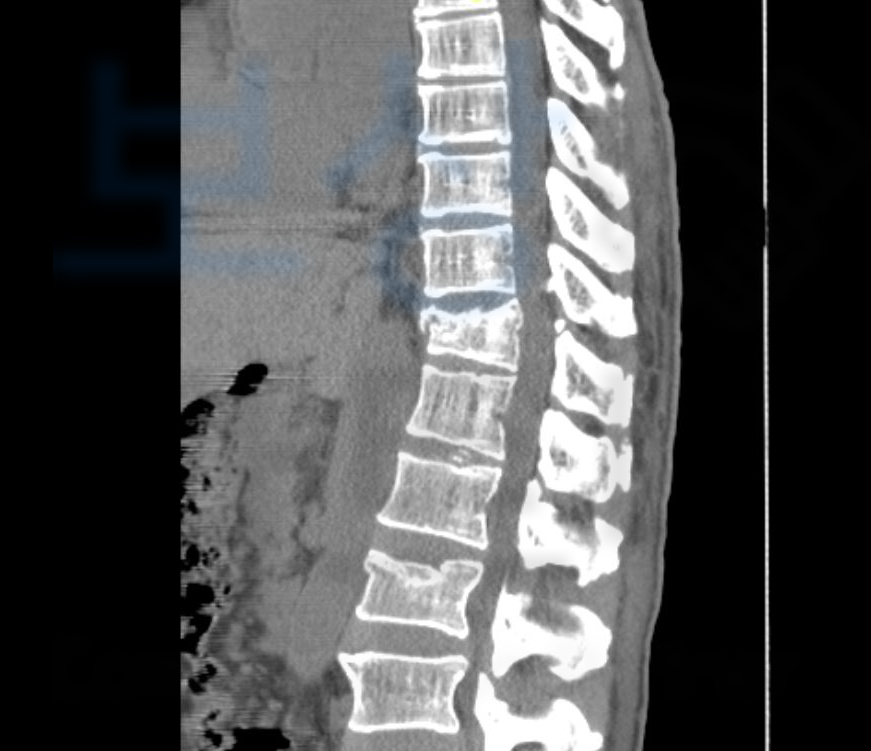

T11, L2 즉 흉추 11번과 요추 2번의

압박골절 진단을 받으셨고 최소 16주간의 요양이 필요했습니다. 하지만 몇 주가 경과했음에도 골절된 척추체는 회복되기 어려웠고 결국 T11에 Kyphoplasty 풍선성형술 L2 는 vertebroplasty 경피적척추성형술 골시멘트술 받게 되었습니다.

척추의 뚜렷한 장해 30%